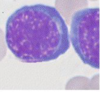

Name the cell indicated by the red arrow #1

Name the cell indicated by the red arrow #2

Name the stain used in the top image.

Name the stain used in the bottom image.

Both are polychromatic erythrocytes.

Top half: Giemsa/Wright stain

Bottom half: supravital stain (new methylene blue or cresyl violet)